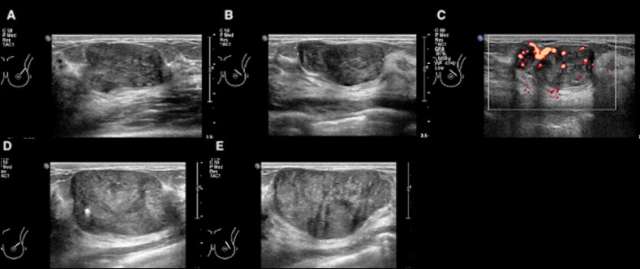

Certain imaging features that may help differentiate a phyllodes tumor from a fibroadenoma include size greater than 3 cm, irregular shape, microlobulated margins, complex heterogeneous echogenicity and internal hypervascularity.2,3 Phyllodes tumors may also be of higher density on mammography given their larger size at presentation.2 On MRI, phyllodes tumors are more likely to demonstrate heterogenous enhancement with internal cystic areas.2 When internal cystic areas are present, phyllodes tumors may demonstrate posterior acoustic enhancement on sonography.